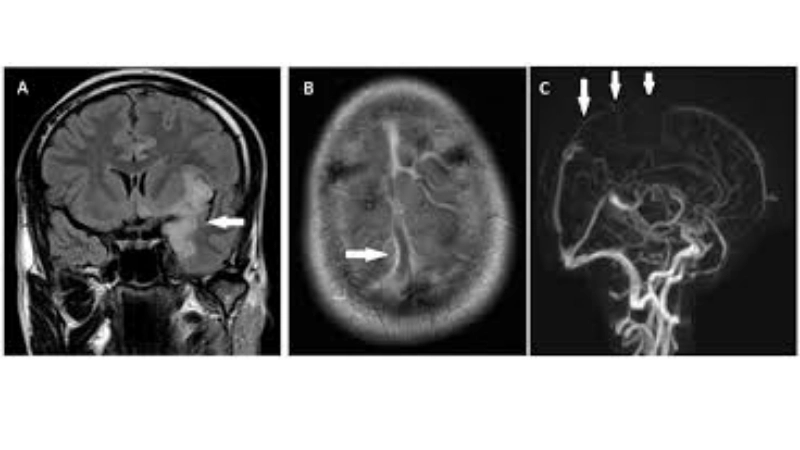

Image description of Herpes Simplex Encephalitis

Herpes Simplex Encephalitis is a rare but serious brain infection caused by herpes simplex virus. It leads to fever, headache, confusion, seizures, and potential long-term neurological damage. Early detection and treatment are crucial for recovery.

Encephalitis diagnosis needs MRI and lab tests